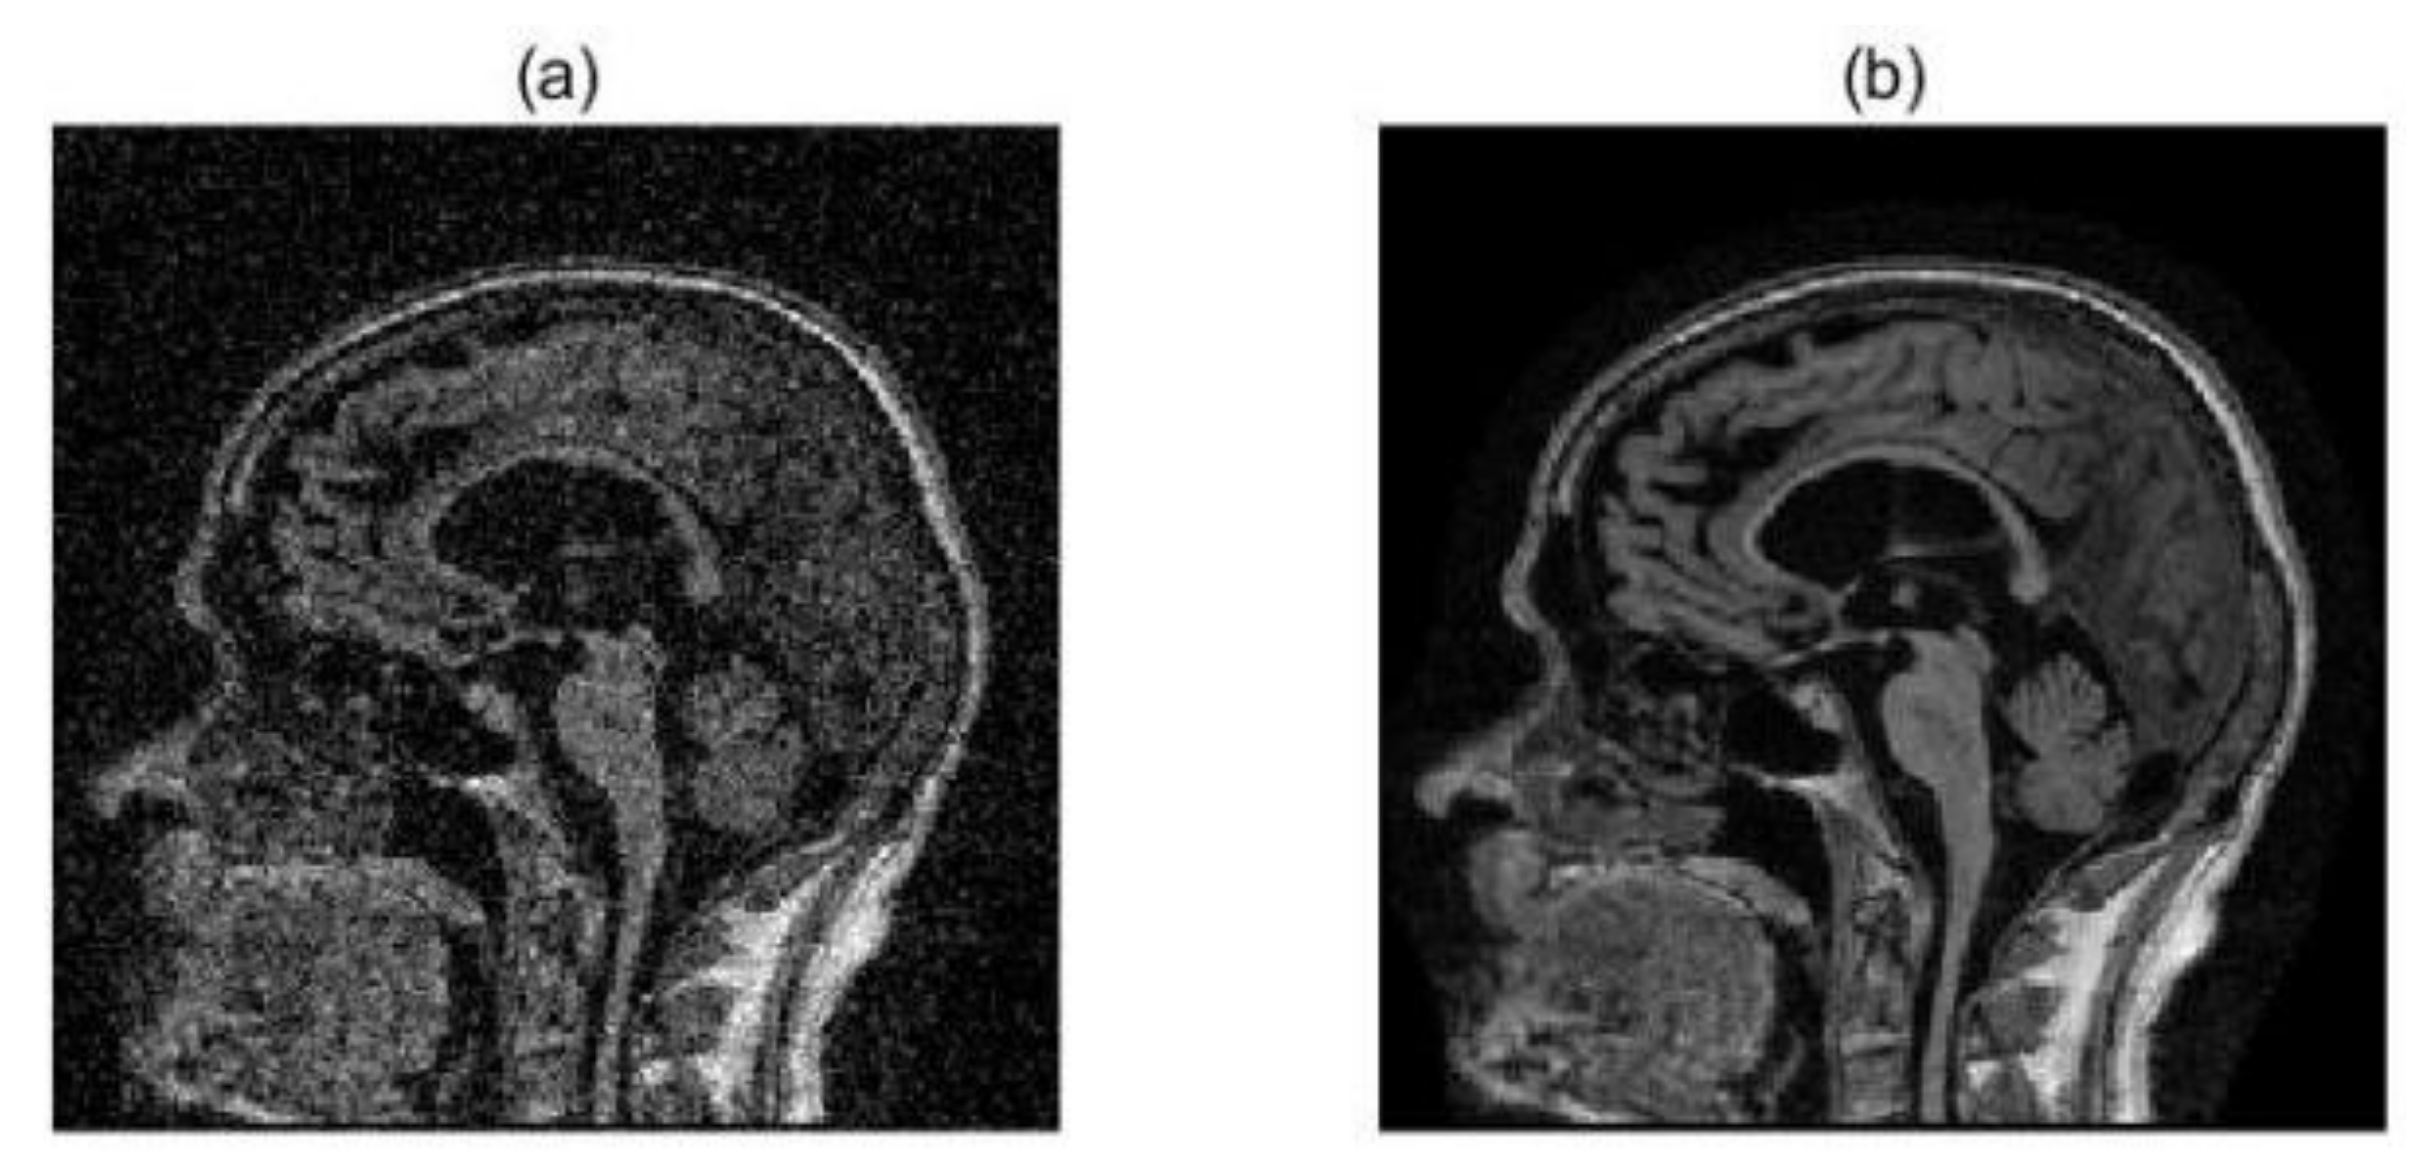

2.2. Image Preprocessing

3.1. Multimodal Image Fusion Results

3.2. Evaluation and Analysis of Fused Images